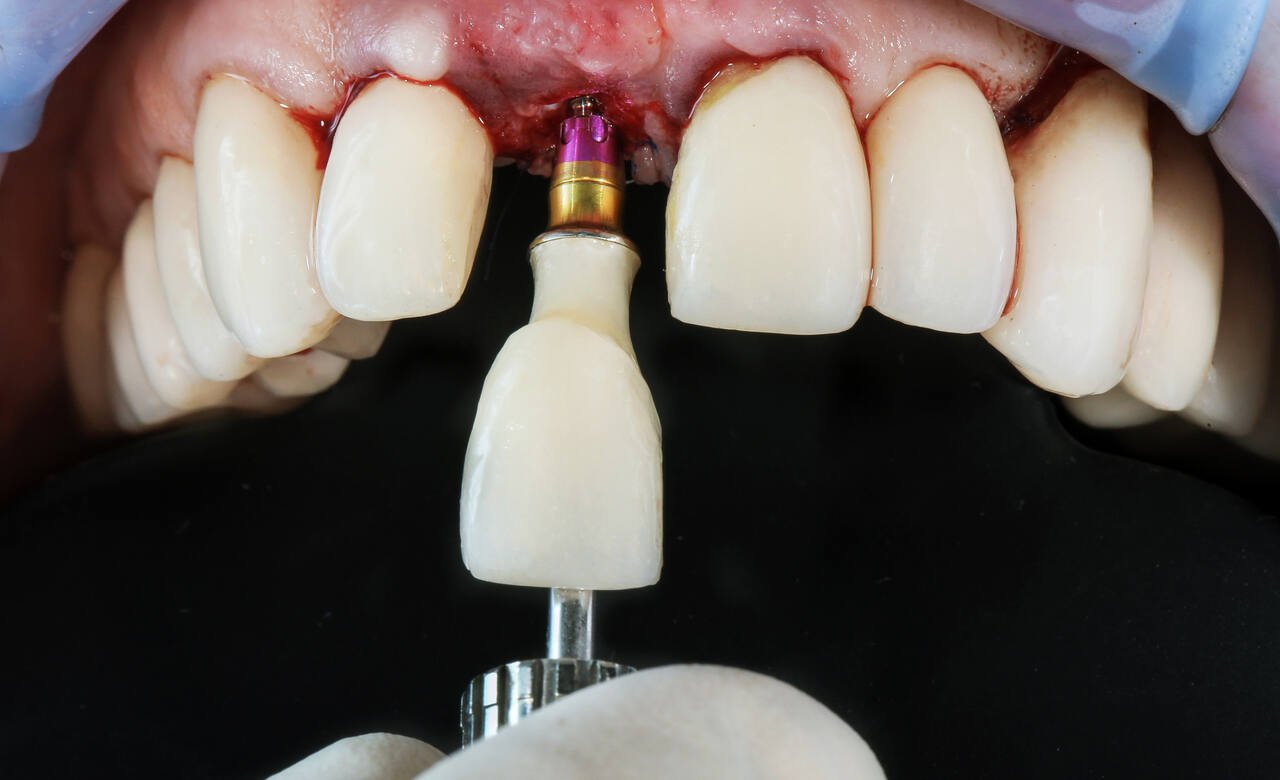

A dental implant is a small titanium screw that is placed inside your jawbone. It works like the root of a natural tooth.

Think of it this way — your original tooth had a root in the bone. The implant replaces that root. A crown (tooth cap) is then placed on top. The result looks, feels, and works exactly like a natural tooth.

Under local anaesthesia (you feel nothing, just some pressure), the titanium implant is placed into the jawbone. The entire procedure takes about 30–45 minutes.

The implant fuses with your bone over 3–4 months. This is called osseointegration. During this time you can have a temporary tooth placed.

Once healed, a custom-made zirconia or PFM crown is placed on top. It is matched exactly to your other teeth in shape and colour.